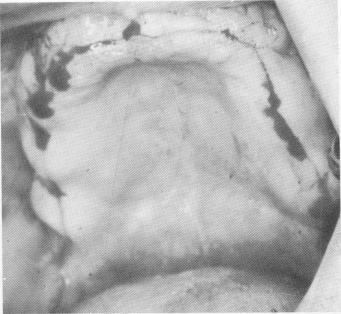

The soft tissue covering the edentulous maxilla was pierced from tuberosity to tuberosity along the crest of the ridge with a sharp scalpel (Fig. 11-167). The tissue was retracted with a periosteal elevator to expose the buccal and labial aspects of the ridge and part of the palatal portion. A groove was created along the center of the ridge from one side of the arch to the other with a No. 700L fissure bur. Its depth was never more than 3 mm. (Fig. 11-168).

Fig. 11-167. The incision is made from retromolar area to retromolar area.

2 Incision made from retromolar area to retromolar area of maxilla